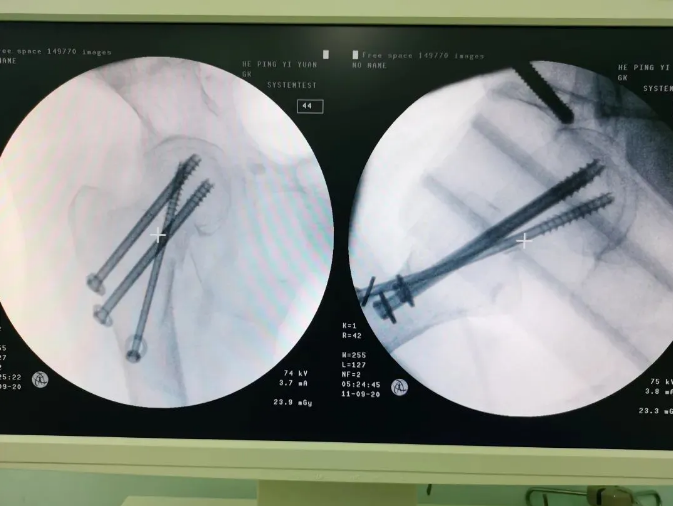

規(guī)劃入路

天璣機(jī)器人置入螺釘

螺釘置入后

天璣?骨科手術(shù)機(jī)器人的加入,能夠協(xié)助醫(yī)生為需要進(jìn)行手術(shù)的患者提供更安全、優(yōu)質(zhì)、高效的醫(yī)療服務(wù),幫助患者清除病灶,守護(hù)患者健康,提高患者生活質(zhì)量。在天璣?骨科手術(shù)機(jī)器人的協(xié)助下,術(shù)中患者切口僅三個(gè)小孔,出血量少;術(shù)后陳婆婆經(jīng)一段時(shí)間的康復(fù)訓(xùn)練便可下床活動(dòng),目前已康復(fù)出院。